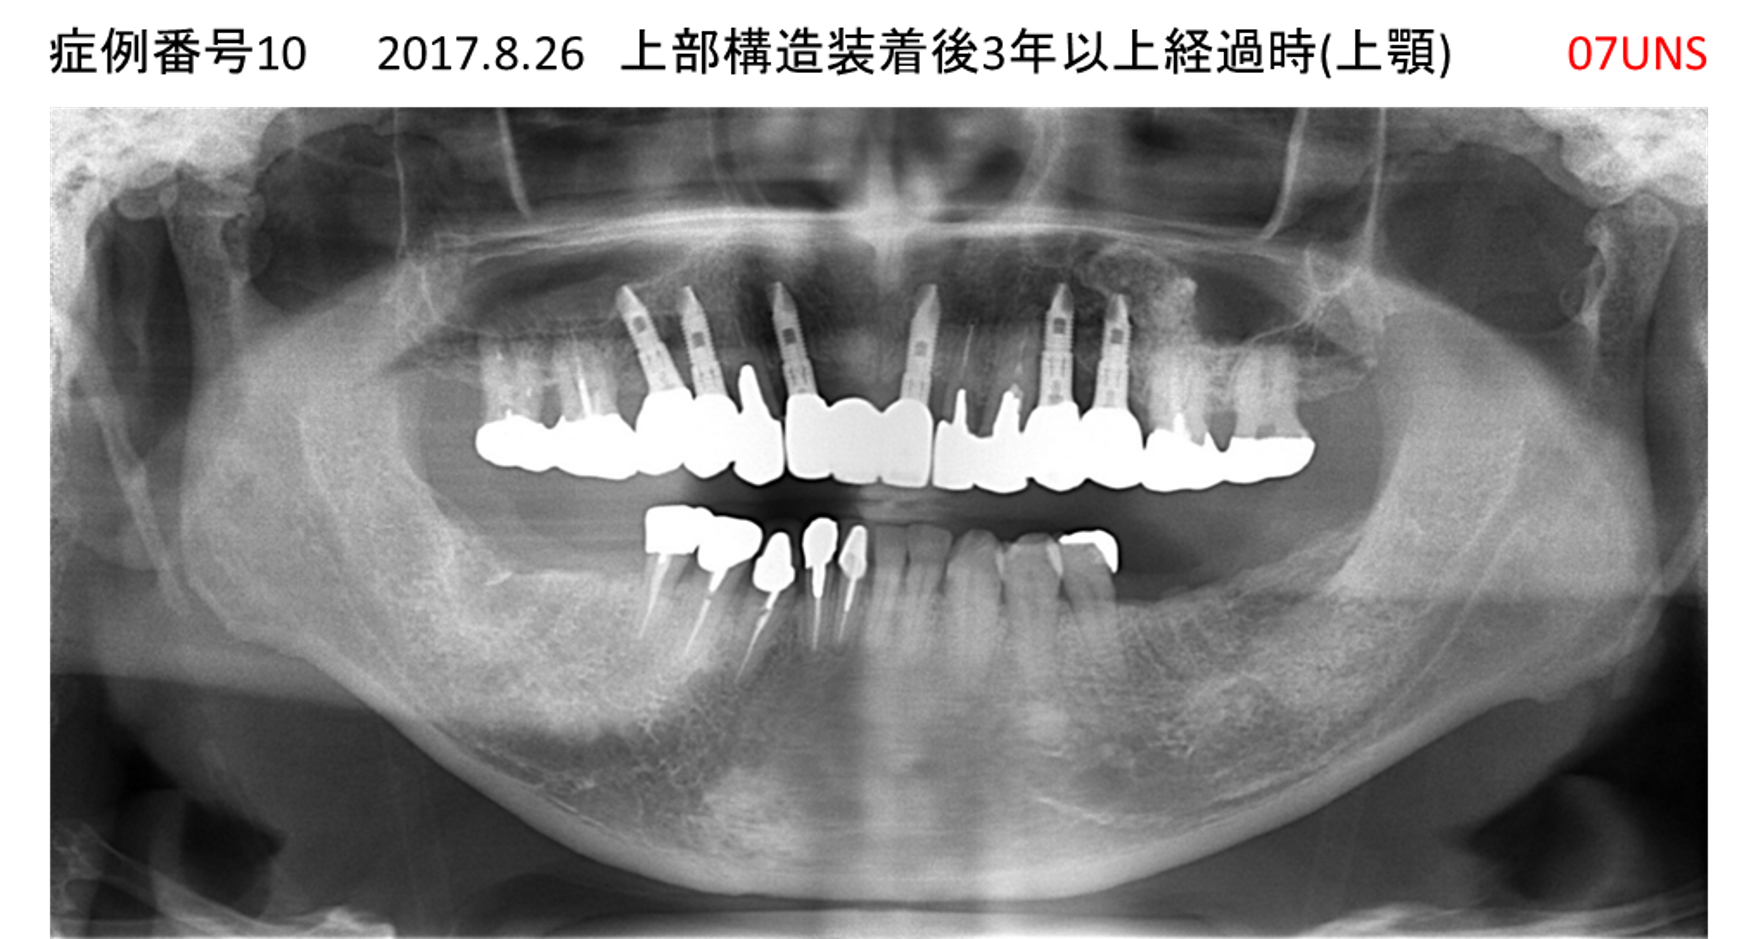

かめない/上の歯が揺れてきた患者様のインプラント症例

| 治療名称 |

インプラント |

| 治療費用 |

390万円+税 |

| 治療期間 |

6か月 |

| 患者さんの症状(主訴) |

かめない。上の歯が揺れてきた。 |

| 治療内容 |

サイナスリフト、抜歯即時インプラント |

| 治療結果 |

上の歯の揺れが収まった。噛めるようになった。食事がおいしい。 |

| 治療の注意点(リスク/副作用) |

インプラントが壊れたら再治療が必要 |